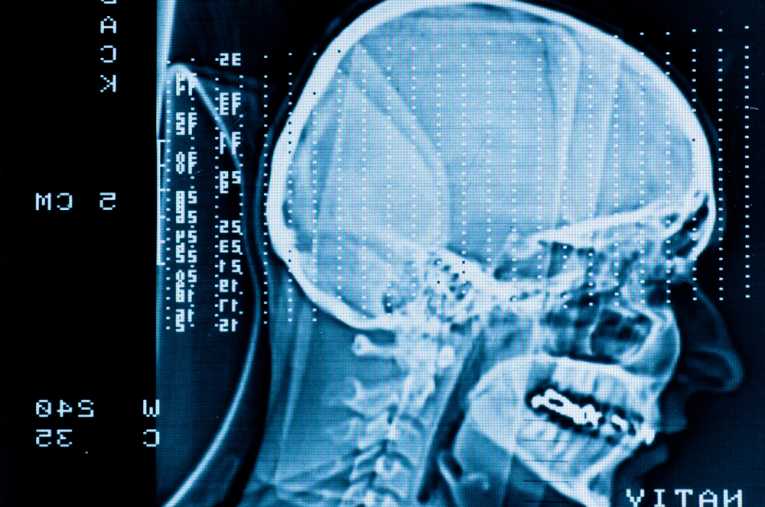

The United States Centers for Disease Control (CDC) has announced that treatments for traumatic brain injury (TBI) among young athletes have increased by 60 percent in the last decade.

Nearly three-fourths of patients treated for TBI in the eight years of the study were male; 70.5 percent of emergency room visits for TBI involved patients aged 10 to 19. Although some evidence has suggested that young brains are more resilient to injury than adult brains, research shows that TBI is actually more dangerous in the young. Recovery times may be longer, and long-term effects more serious.

While TBI symptoms may seem mild, the injury can result in life-long impairment, including loss of memory, changes in behavior, learning ability and emotions. Experts caution that it is always better to be safe than sorry. Children should be examined by a health care professional whenever a head injury is believed to have occurred.